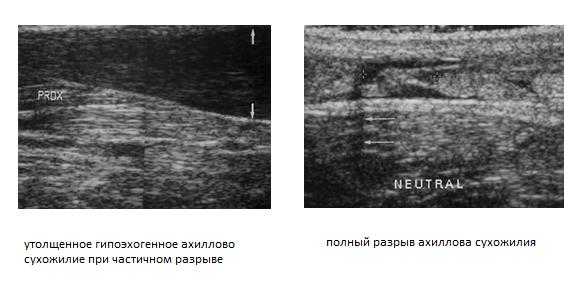

Клинический осмотр и применение диагностических тестов позволяют точно установить диагноз у 70% больных. На помощь специалисту приходят такие методы как сонография (УЗИ) и МРТ. Сонография - очень точный, быстрый, малоинвазивный и дешёвый метод диагностики разрывов ахиллова сухожилия - но только в руках опытного специалиста. Позволяет отличить частичные и полные разрывы.

Опытный специалист может быть с успехом заменён на качественное программное обеспечение и использование высокопольного МРТ.